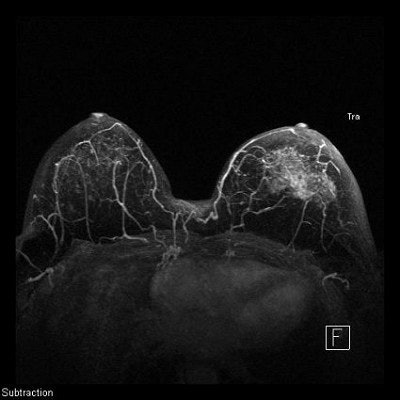

For lobular cancer diagnosis, Porter relies on a series of MIPs acquired over time to allow gadolinium contrast to leak, pool, and enhance tumor vessels.

The diffuse infiltrative nature of lobular carcinoma makes it difficult to detect. Two-minute (top), four-minute (middle), and thin-MIP (below) views demonstrate contrast enhancement in tumor tendrils over time. Images courtesy of Dr. Bruce Porter, First Hill Diagnostic Imaging.